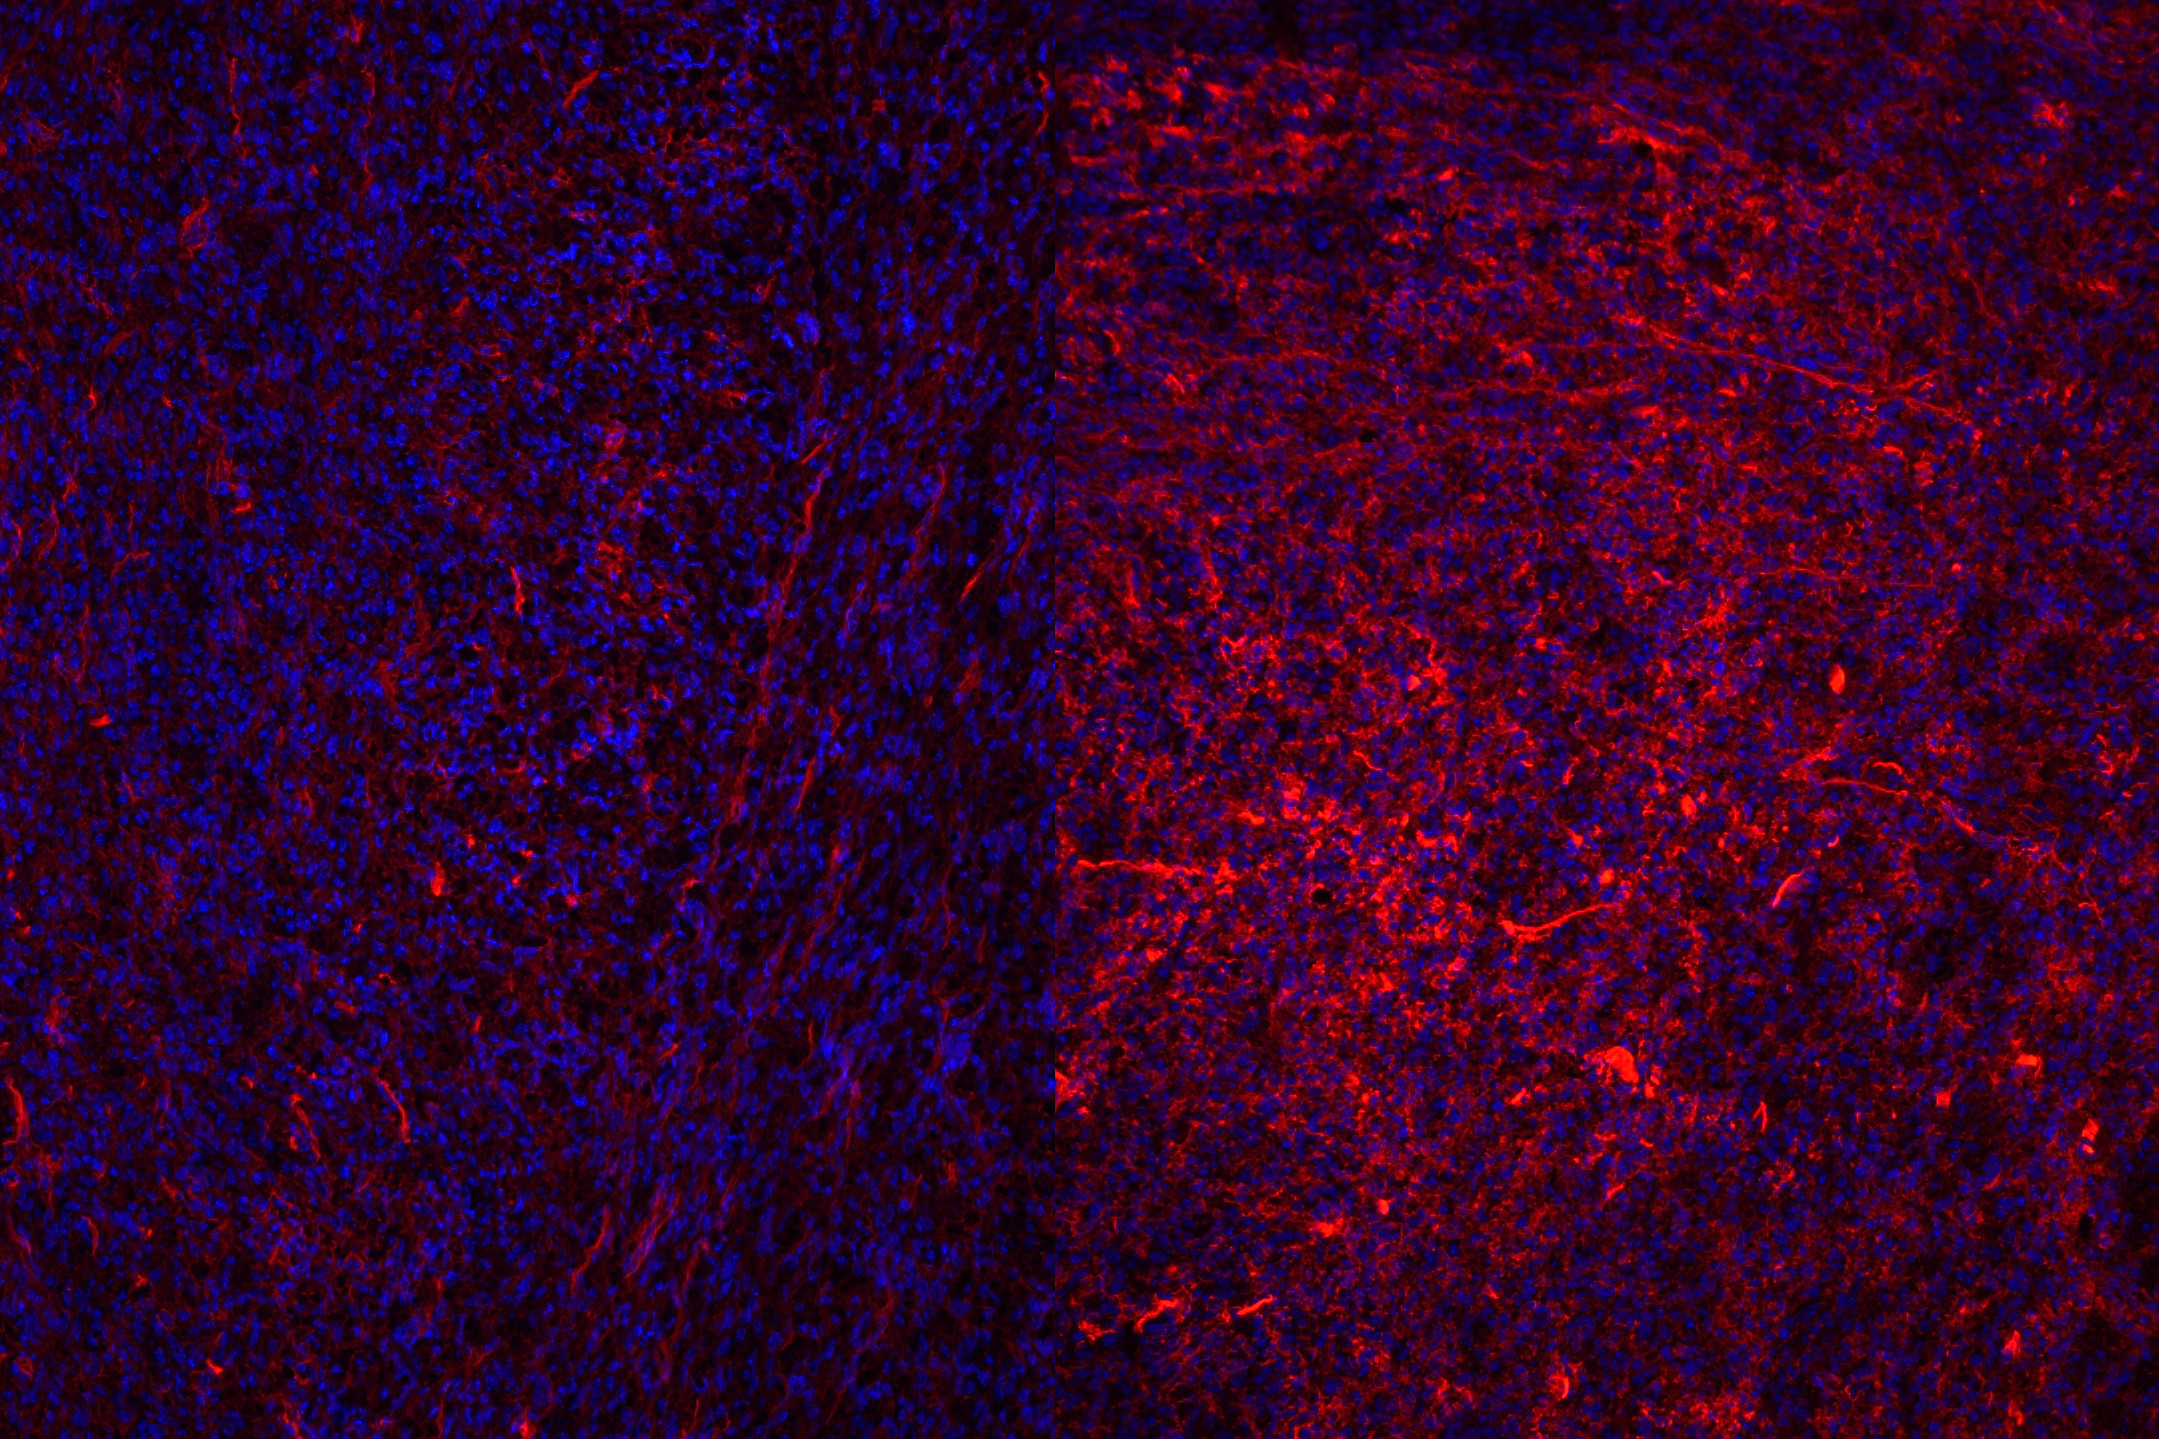

The team made two discoveries. First, they explained why even the most powerful targeted therapeutics can fail: they showed that the thickened matrix acts like a physical barrier, preventing cytotoxic T cells, the immune cells that directly kill cancer, from reaching the tumor. “It changes the way we think about cancer treatment, from focusing only on the cancer cells themselves to understanding and treating the entire tissue environment around them,” Hsu said.

Second, using drugs that reduced or loosened this matrix allowed T cells re-enter the tumor and attack the tumor again. “It was thrilling to see how changing the extracellular matrix (ECM) could completely reshape the immune landscape of a tumor. Under the microscope, we could literally see cytotoxic T cells spreading more evenly once the ECM was reduced. It felt like uncovering a hidden mechanism that had been holding back the immune system from doing its job,” Hsu said.